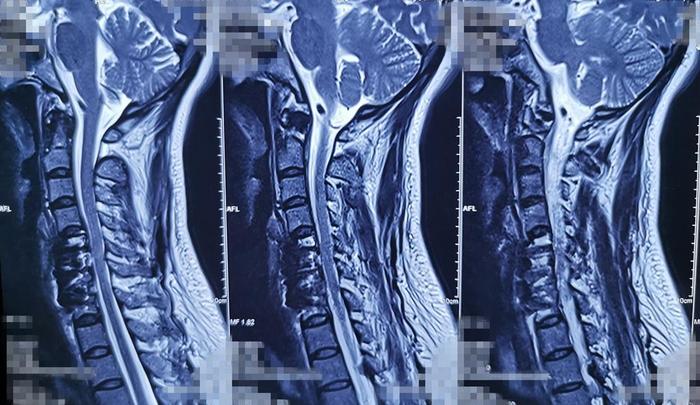

术前影像学资料

廖博主任为周女士做了详细的检查,检查结果发现周女士颈椎间盘突出(颈5-7)、颈椎生理曲度变直、骨质增生。廖主任告诉周女士:“从目前的检查和症状表现来看,你的颈椎病情况比较严重,建议手术治疗。”周女士一听到要手术治疗,感觉很惊讶,心里在想“很普遍的颈椎病,没听说过要手术治疗的”。

“右手的疼痛、麻木就是明显的手术指征,这是由于颈椎间盘突出,已经压迫到了临近的脊髓和神经根,如果长时间受压,很可能出现更严重的症状,比如四肢的麻木,甚至有瘫痪的风险!”廖主任进一步解说着。